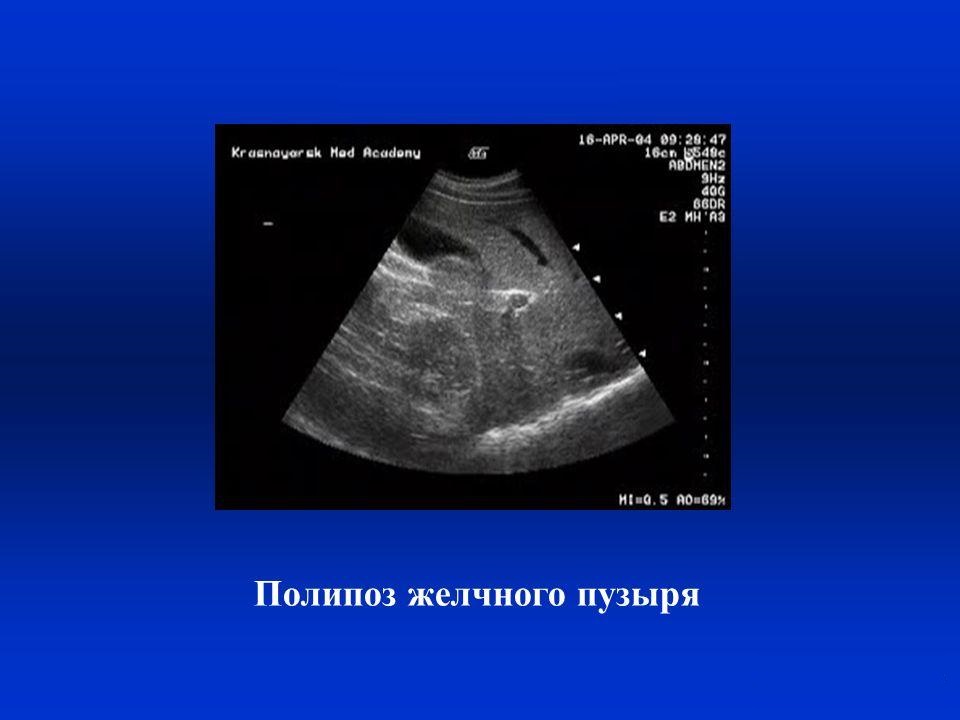

Одиночные полипы в желчном (в количестве до трех штук) в медицине так и называются, а если таких образований много – болезнь называется полипозом. От размеров, вида и количества этих патологических образований зависит метод их лечения.

- Ультразвуковое исследование (всем известное УЗИ). С его помощью врач может увидеть плотно прилегающие к стенкам органа округлые образования, которые смещаются при перемене пациентом положения тела (в отличие от камней);